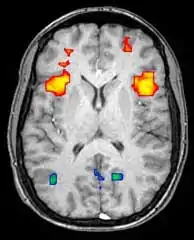

Функциональная магнитно-резонансная томография

Функциональная магнитно-резонансная томография (фМРТ) основана на парамагнитных свойствах оксигенированого и дезоксигенированого гемоглобина и дает возможность увидеть изменения кровообращения головного мозга в зависимости от его активности. Такие изображения показывают, какие участки мозга активированы (и каким образом) при исполнении определённых заданий.

Большинство фМРТ-томографов дают возможность представлять исследуемому разные визуальные изображения, звуковые и тактильные стимулы и производить действия типа нажатия кнопки или движения джойстиком. Следовательно, фМРТ можно использовать, чтобы показывать структуры мозга и процессы, связанные с восприятием, мышлением и движениями. Разрешение фМРТ на данный момент 2—3 мм, ограниченное кровоснабжением, влияющим на нейрональную активность. Она существенно заменяет ПЭТ при исследовании типов активации головного мозга. ПЭТ, однако, одерживает значительное преимущество, будучи в состоянии идентифицировать специфические клеточные рецепторы или (моноаминовые трансмиттеры) связанные с нейромедиаторами, благодаря визуализации меченных радиоактивно рецепторных «лигандов» (рецепторный лиганд — химическое вещество, связанное с рецептором).

фМРТ используют как для медицинских исследований, так и (всё шире) в диагностических целях. Так как фМРТ исключительно чувствительна к изменениям кровообращения, она очень хорошо диагностирует ишемию, как например при инсульте. Ранняя диагностика инсультов всё важнее в неврологии, так как медикаменты, растворяющие свернувшиеся сгустки крови можно использовать в первые несколько часов и при определённом типе инсульта, в то время как они могут быть опасными при дальнейшем использовании. фМРТ в таких случаях дает возможность принять правильное решение.

фМРТ можно использовать также для распознавания мыслей. В эксперименте с точностью 72 %—90 %[5] фМРТ смогла установить, какой набор картинок смотрит испытуемый[6]. Скоро, по мнению авторов исследований, благодаря этой технологии можно будет установить, что именно видит перед собой испытуемый[6]. Эту технологию можно будет использовать для визуализации снов, раннего предупреждения болезней головного мозга, создания интерфейсов для парализованных людей для общения с окружающим миром, маркетинговые рекламные программы и борьба с терроризмом и преступностью[6].